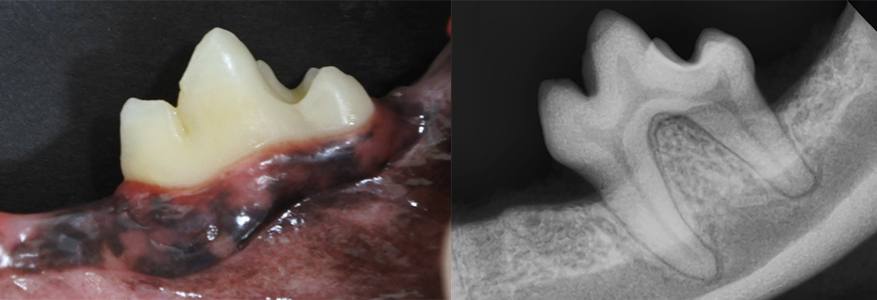

この画像は治療時の歯科X線画像です。

歯根長(水色矢印)の半分以上の骨欠損像(黄色矢印)が認められるため、ステージ4の重度歯周病です。通常は抜歯を検討する重度な歯周病です。

右の画像は治療半年後のメインテナンス時の歯科X線画像です。

歯槽骨の回復が認められます。

プロケアである当院での治療と、ホームケアである飼い主様の歯磨きにより、歯の温存が可能であった一例です。